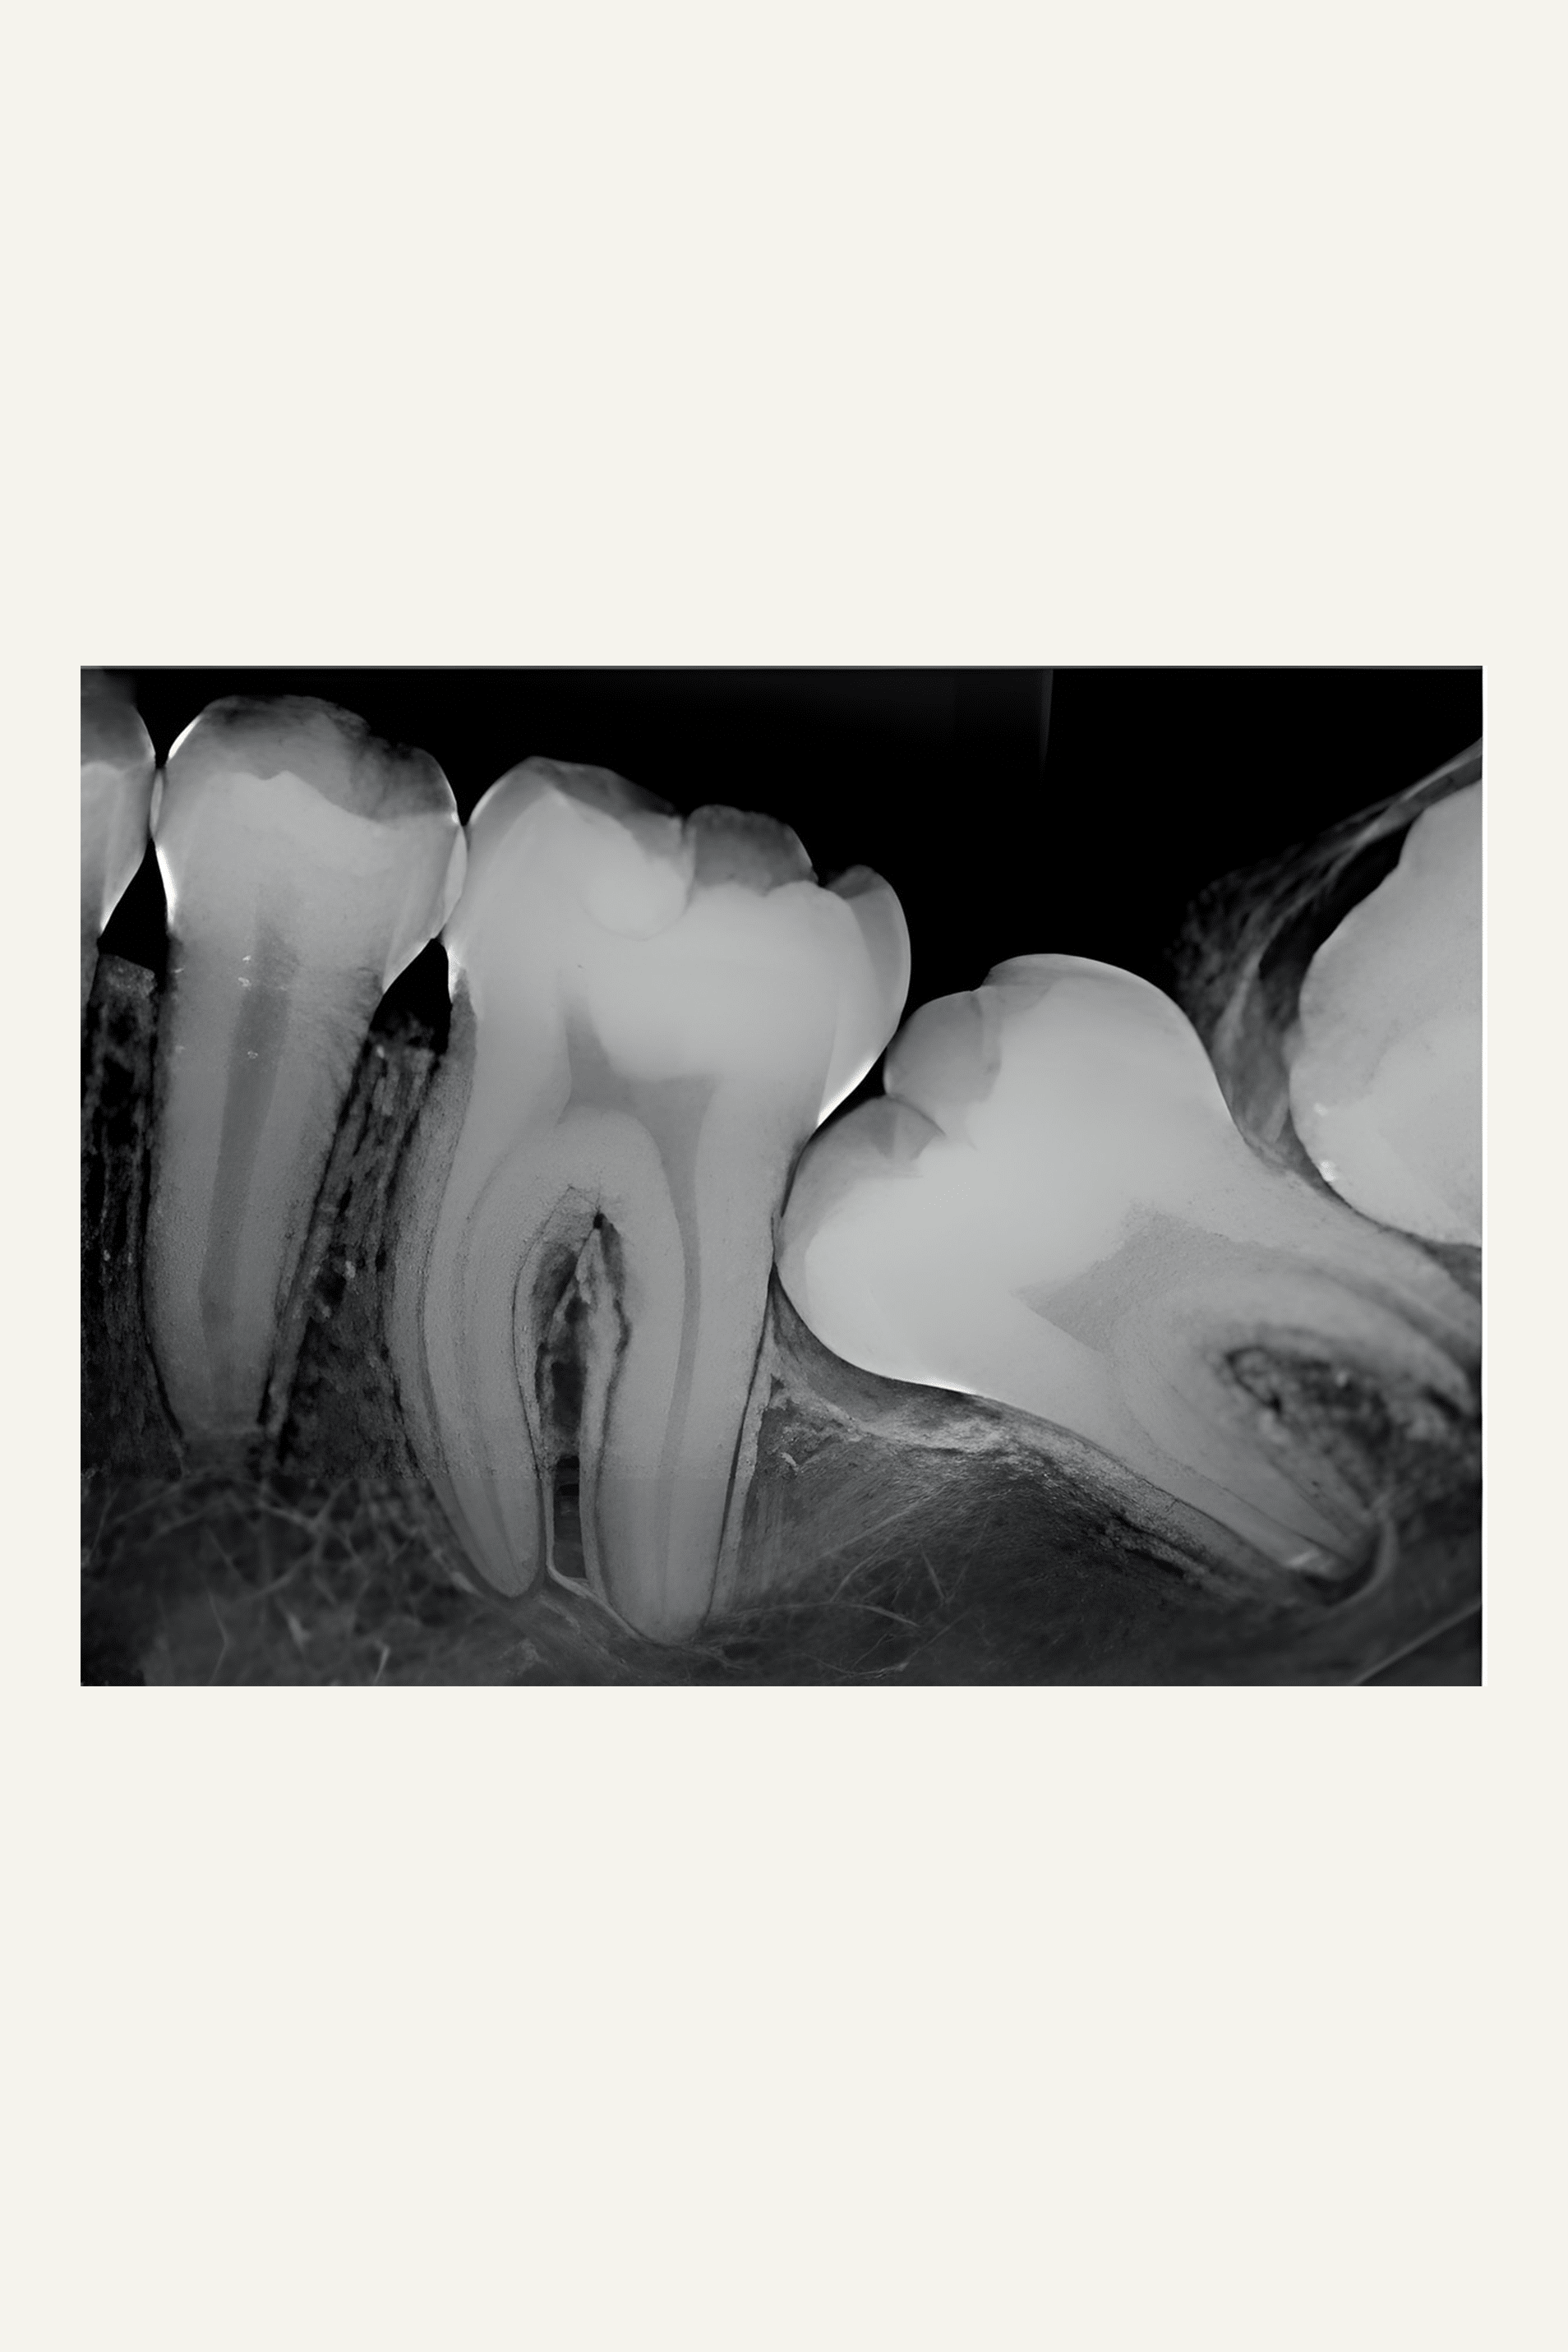

Hos Tandlægerne i Gistrup er vi uddannet til at fjerne komplicerede tænder, som ligger uhensigtsmæssigt i mundhulen. Som regel drejer det sig om visdomstænder i underkæben, som kan ligge vandret. Disse tænder skal fjernes kirurgisk ved at lægge slimhinden til side, fjerne lidt knogle omkring tanden, dele tanden og afslutningsvis vippe tandstykkerne ud med det vi kalder en elevator. Efter operationen skylles med sterilt saltvand og der lægges et par sutur.

Hvis tænderne eksempelvis ligger oven i nerven, der går til alle underkæbe tænder eller der ses en stor cyste omkring en visdomstand vil vi henvise til specialkirurg Mette Marcussen. I disse tilfælde kan man ikke nøjes med et almindeligt røntgenbillede for at lokalisere tanden og omgivelserne. Her kan det være nødvendigt med et CT-scan eller et panoramarøntgen før operationen, så man undgår nerveskade i området efter operationen.